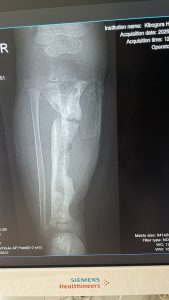

Darunter befand sich auch Claude, den die Ärzte der Osteomyelitishilfe schon früher operiert hatten.

Er hatte eine deutliche Beinverkürzung und Rekurvationsfehlstellung links bei straffer Tibiapseudarthrose.

Claude konnte zwar schmerzfrei gehen, aber es sah schon sehr beschwerlich aus. Hier ist eine Korrekturoperation in mehreren Schritten angezeigt. Wir werden diesen Fall mit den Ärzten der Unfallchirurgie besprechen.